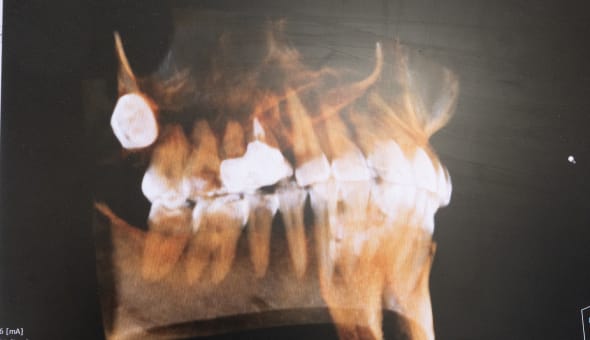

高度な治療当院では「保険適応外の自費診療」とさせていただいております。これにより、保険では対応できない高度な治療、最新の医療材料を使うことが可能で、なるべく『削らず』『抜かない』施術を実現することで、歯の寿命を延ばすことが期待できます。日々、医学知識や技術力の向上に努め、CTやマイクロスコープを使った、より精度の高い歯科医療をご提供しています。

マイクロスコープによる精密根管治療 -